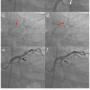

Case Report. A 40-year-old male patient with multiple coronary risk factors of hypertension, hyperlipidemia, diabetes mellitus and hyperuricemia was admitted to our hospital because of angina pectoris. He had established end-stage renal disease and had already been on hemodialysis before admission. Coronary angiography showed a CTO of the proximal left circumflex (LCx) artery combined with steep angulation (Figures 1a and b). PCI was performed using an antegrade approach. A 6 Fr BL 4.0 Heartrail guiding catheter (Terumo)

or a 7 Fr BLH Brite tip guiding catheter (Cordis) was used via the right femoral artery. We tried to proceed the Finecross microcatheter, (Terumo) to the completely occluded LCx artery using a Rinato guidewire (Asahi Intecc), but multiple attempts to deliver the micro-catheter to the LCx occlusion were unsuccessful due to the prolapse of microcatheter into the patent left anterior descending (LAD) artery (Figures 1c and d). The extremely steep angle of LCx artery in its take-off from the very large left main trunk seemed to the cause of the difficulty to advance the microcatheter. To take more co-axial direction to the LCx artery, the guiding catheter was changed to a 6 Fr Amplatz 3.0 Heartrail guiding catheter. Then, an X-treme guidewire (Asahi Intecc) was used to select the atrial branch for a Finecross micro-catheter delivery (Figure 1e) and the Finecross micro-catheter could successfully cross the steep angle of LCx artery (Figure 1f). Subsequently, an X-treme guidewire and the Finecross micro-catheter were further advanced toward the proximal part of the CTO lesion. A Wizard 3 (Japan Lifeline), a Miracle 6, and a Conquest Pro guidewire (Asahi Intecc) were used to cross this CTO lesion but were unsuccessful because of insufficient backup guidewire support (Figures 2a and b). Therefore, we changed the micro-catheter to a Corsair micro-catheter. A Corsair micro-catheter was easily advanced toward the just proximal part of the CTO lesion using a similar method. Finally, the Conquest Pro guidewire (Asahi Intecc) was able to cross this CTO lesion (Figure 2c). Although a Corsair micro-catheter was not able to cross this CTO lesion, a 1.25-mm x 10-mm Tazuna balloon (Terumo) was able to cross and successfully dilated the CTO lesion. A 2.5-mm x 15-mm Signet Pro balloon (St. Jude Medical) was then used to open this CTO lesion further. Stent implantation was successfully performed using a 3.5-mm x 23-mm Xience V stent (Abbott). Final coronary angiogram showed a satisfactory result without any complications (Figures 2d and 2e).